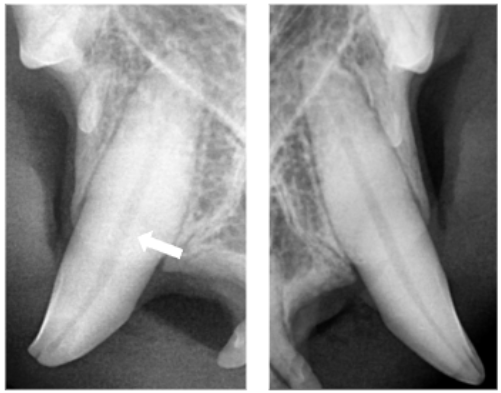

송곳니 치과 방사선 사진에서도 우측 송곳니 끝이 파절되어 있었고

정상 치아와 비교했을 때 치수강이 확장된 모습이 관찰되었습니다.

이미 세균이 치아 안쪽으로 침투하면서 치수염이 진행된 상태였습니다.

치료 후 사진에서도 근관 충전이 잘 이루어진 것을 확인할 수 있었고,

무사히 치료를 마쳤습니다.